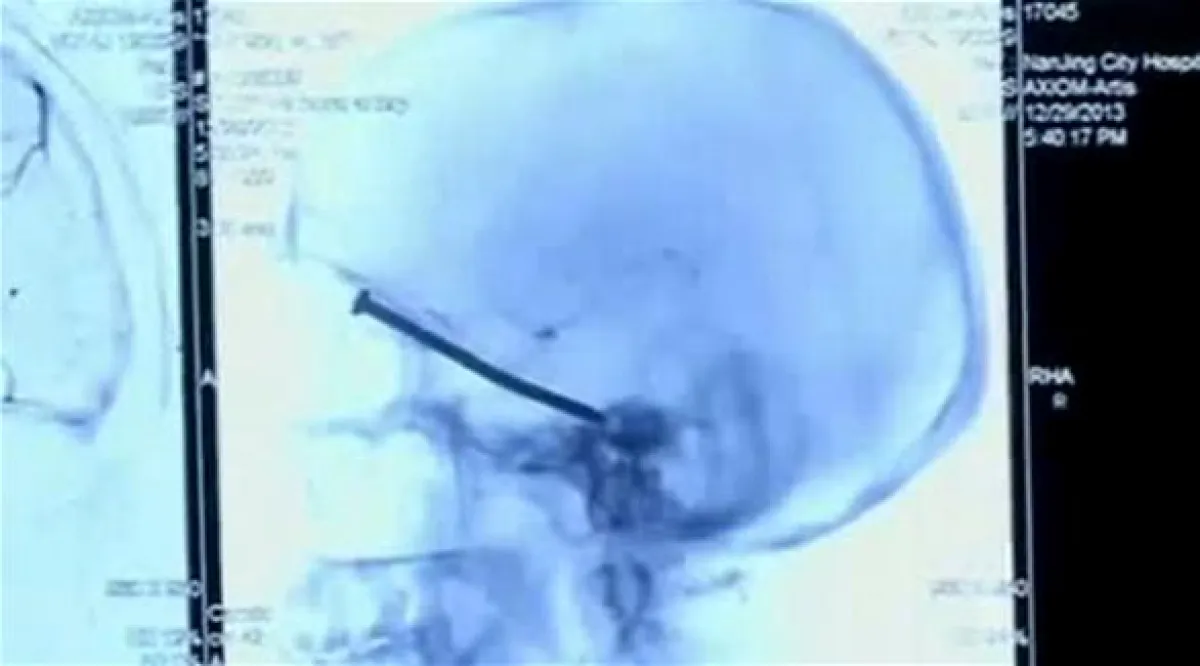

يبدو أن مقولة "العين عليها حارس!" حقيقة، فبأعجوبة تمكن الجراحون من إنقاذ شاب صيني غُزر مسمار طوله 3 إنش بالقرب من محجر عينه اليسرى لتستقر في نهاية المطاف داخل رأسه، والغريب أنه لم يكتشف وجود المسمار الصلب بجمجمته إلا عند الذهاب إلى المستشفى وإجراء الأشعة والفحوصات التي أظهرت ذلك.

وعن طريق الخطأ تعرض يانغ يي كوي (55 عاماً) من مقاطعة جيانغسو الصينية لهذه الحادثة أثناء استخدامه آلة قطع خلال تزيين منزله في 29 ديسمبر (كانون الأول)، فكان المسمار الصلب موجوداً داخل الآلة، فانبثق فجأة بسرعة الصاروخ من الآلة ليستقر داخل الدماغ تاركاً فقط حفرة صغيرة في فروة الرأس، وتمكن كوي من معالجتها كأي جرح أو خدش دون أن يعي أو يولي اهتماماً يُذكر بهذا الجرح الصغير، ولم يرد في خاطره على الإطلاق بأن المسمار اخترق جمجمته بل اصطدم برأسه فقط.

وعندما شعر كوي بألم لا يحتمل ومتواصل في رأسه، توجه على الفور إلى المستشفى، ليكتشف بمحض الصدفة وعن طريق الأشعة المقطعية وجود مسمار صلب طوله 3 إنش، فأجرى الأطباء عملية جراحية سريعة لإخراج هذا المسمار من رأسه، بعد أن توغل داخل السائل الدماغي ليستقر بقرب محجر العين اليسرى، دون أن يتسبب بأي ضرر أو أذى يُذكر في الدماغ أو العين، وأكد الأطباء أن حالة يانغ في الوقت الراهن مستقرة ولكنه لا يزال يمكث داخل المستشفى لمتابعة حالته أولاً بأول